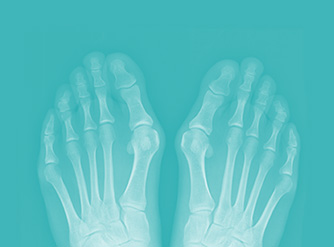

Controllo Radiografico

Dopo 45 giorni dall’intervento, visita di controllo con il medico chirurgo -radiografie carico ortostatico- per verificare lo stato di calcificazione, il consolidamento e l’allineamento delle ossa del piede...

Alluce Valgo

L’alluce valgo è una patologia del piede che colpisce numerose persone, soprattutto donne. Si tratta di una malattia invalidante, le cui cause non sono del tutto conosciute anche se la sua manifestazione è spesso legata ad un…